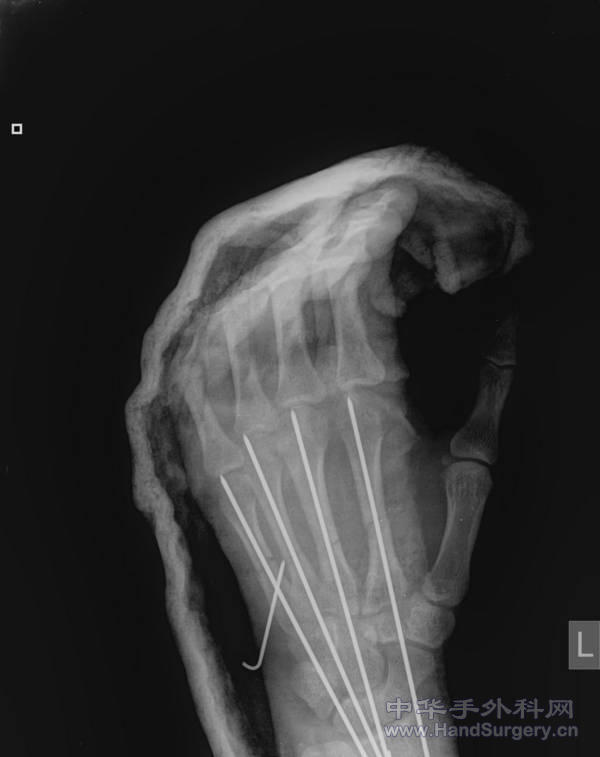

术后1月,准备去除石膏,加强功能锻炼。